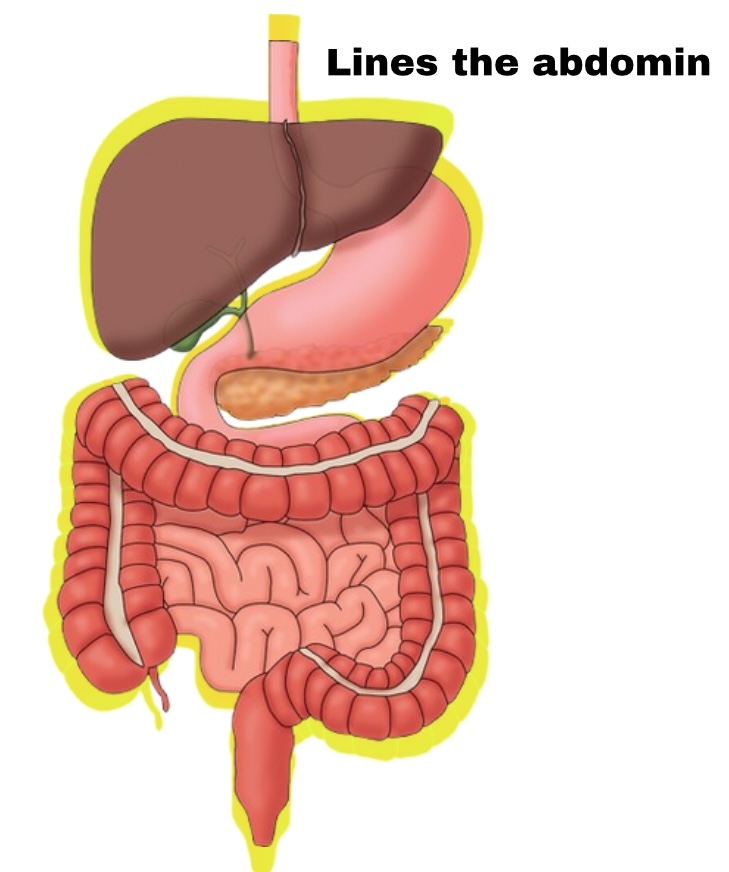

Peritoneum

Membrane lining abdomen

Partial Peritoneum

Outer layer

Visceral Peritoneum

Deep layer (surface of organ)